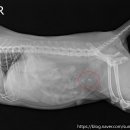

환자들의 후기 등을 미리 살펴보는 것이 도움이 될 수 있습니다. ​ 다음으로, 병원의 시설과 장비 역시 중요한 고려 사항입니다. 최신 진단 장비(예: X-ray, 초음파, 혈액 검사 장비)를 갖추고 있는지, 수술실이나 입원실의 위생 상태는 어떠한지 등을 확인해야 합니다. 특히 응급 상황 발생 시 신속하고 정확한 진단과...

• 선부중앙동물의료센터 | 강아지 요로 결석 재발 재수술 후기

​ ​ ​ 강아지 결석 재발 재수술 후기 강아지 요로결석, 방광결석 재발로 재수술하게 된 후기 남겨봅니다. 반려견 결석은 재발률이 높은 편이라고 해서 꾸준히 관리...이번 수술은 선부중앙동물의료센터에서 진행했어요. ​ ​ ​ ​ 📍선부중앙동물의료센터 정보 주소 : 경기 안산시 단원구 선부광장1로 69 단지내상가동 2층...